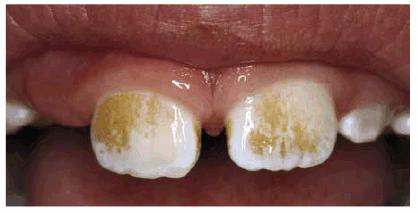

Figure 16-12A and B: Trauma to primary teeth can result in a large white-spot discoloration (A) or a less noticeable white and brown defect (B).